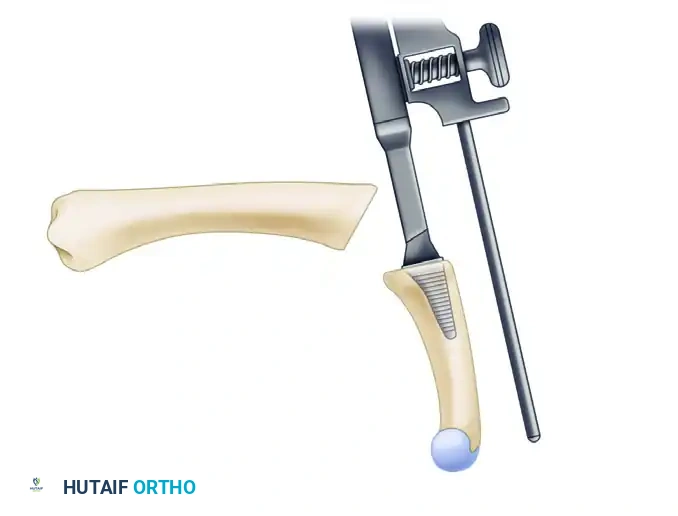

3. Joint Preparation and Bone Resection

- Metacarpal Resection: Resect the metacarpal head perpendicular to the long axis of the metacarpal shaft. It is critical to leave the metaphyseal flare of the metacarpal intact to provide a broad, stable base for the implant hinge.

- Proximal Phalanx Preparation: Leave the base of the proximal phalanx intact whenever possible. However, if additional space is required to accommodate the hinge of the prosthesis without buckling, remove a minimal portion of the articular cartilage and subchondral bone using an oscillating saw or rongeur.

4. Canal Preparation and Trialing

- Utilize specialized broaches and reamers to prepare the medullary canals of both the metacarpal and the proximal phalanx.

- Insert temporary trial prostheses to determine the optimal size. The goal is to select the largest size that the metacarpal shaft will comfortably accept without causing cortical fracturing. The implant stems should fit snugly, and the central hinge should sit flush against the resected bone surfaces.

5. Preparation for Soft Tissue Reconstruction

- Before inserting the final implant, prepare the proximal phalanx for the reattachment of the EPB.

- Drill small osseous holes in the dorsal base of the proximal phalanx.

- Pass a robust, non-absorbable suture (e.g., 2-0 FiberWire or Ethibond) through these holes so that it is pre-positioned for the reattachment of the EPB after the prosthesis has been seated.

6. Implant Insertion

- Thoroughly irrigate the medullary canals to remove bone debris and marrow fat.

- Insert the final silicone implant using a "no-touch" technique with smooth forceps to avoid scratching the elastomer, which can create stress risers and lead to premature failure.

- Optional: If needed due to irregular, sharp, or cystic bony surfaces, insert metal sleeve "grommets" into the canals prior to the silicone implant. These titanium shields protect the silicone hinge from abrasive shear forces.